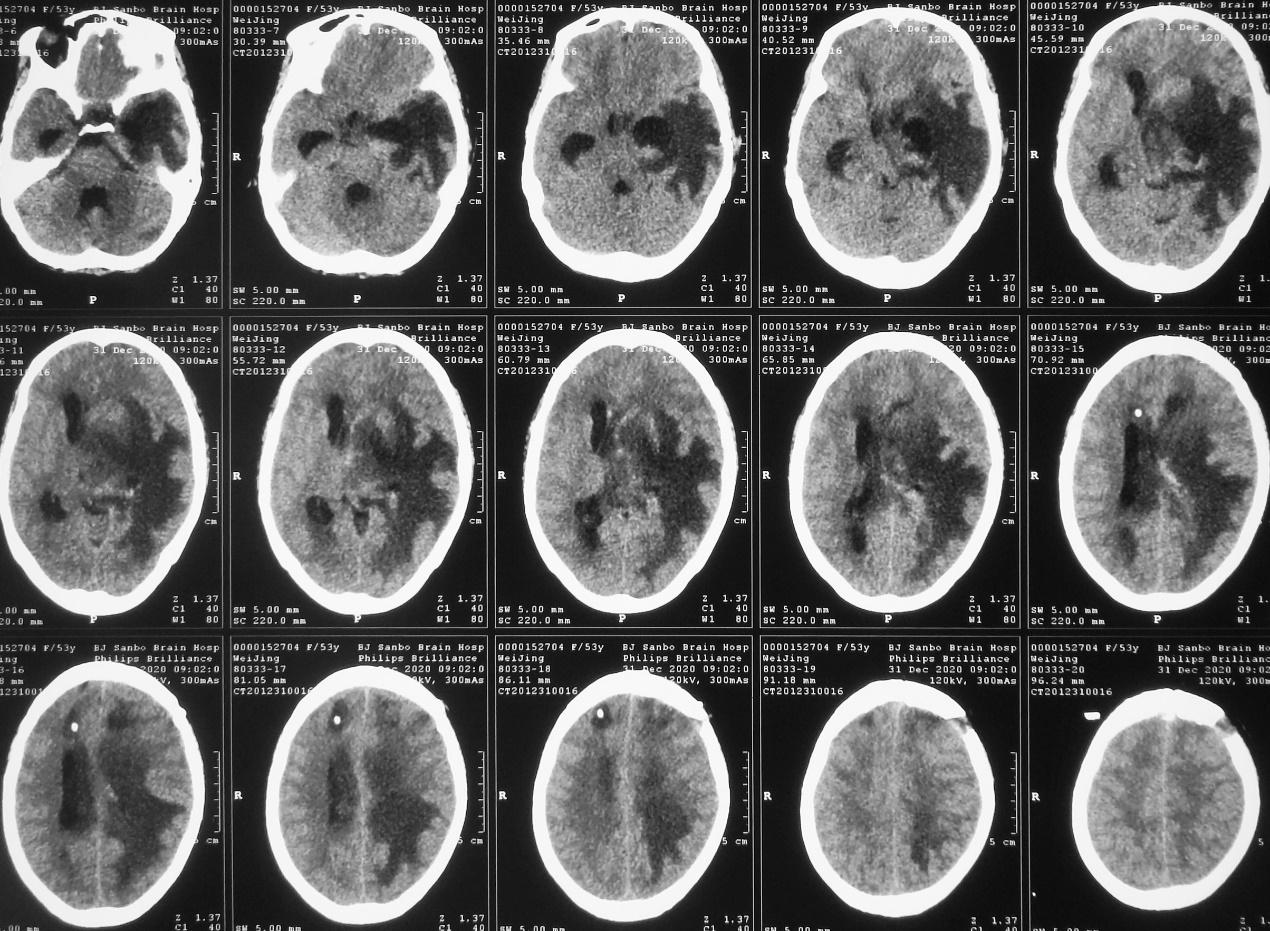

脑脓肿清除术后第23天,拔除外左侧脑室颞角引流管后第6天,即2020年12月31日,患者再次出现昏迷,复查头颅CT( 图-20 )见左侧脑室颞角扩张,右侧脑室引流管脱出。当天再次行左颞角穿刺引流术,同时调整右侧脑室引流管深度后引流通畅。

图-20: 2020年12月31日头CT

第二次左侧颞角引流术后第1天,即2021年1月1日,患者神志明显好转,清醒,可遵嘱动作,复查头颅CT见各脑室较前均缩小( 图-21 )。

图-21: 2021年1月1日头CT